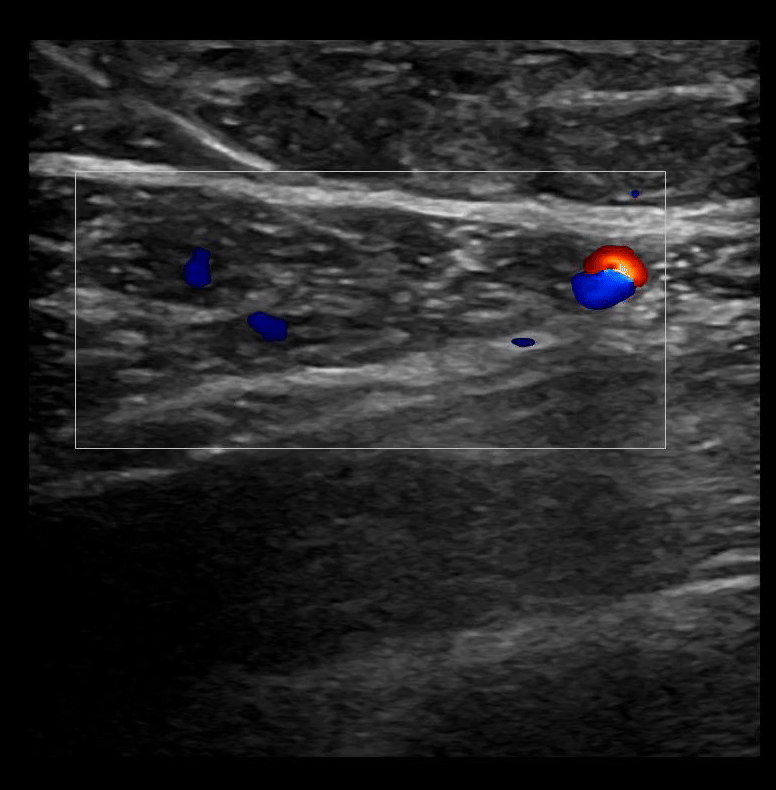

SAPB 2: The latissimus dorsi muscle sits superficial to the serratus anterior muscle. A color box on the latissimus dorsi muscle identifies vasculature.